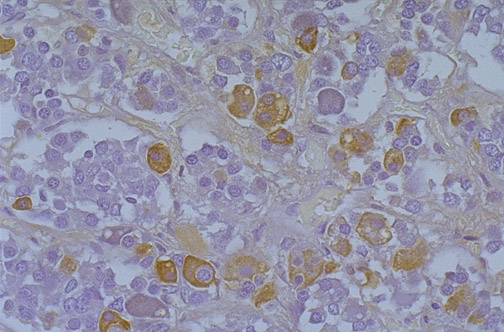

There are cells seen here in normal adenohypophysis that stain for human growth hormone.